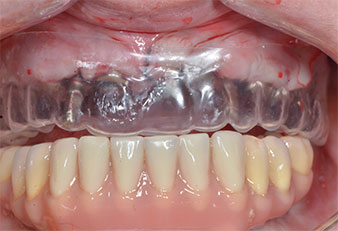

Wegen des relativ harten Knochens (D2) an den Positionen 11 und 21 wurden die 10 mm langen Implantatlager in diesem Bereich abschließend mit einem 4-mm-Spiralbohrer, dem chirurgischen Winkelstück WS-75 L von W&H und dem W&H Implantmed Implantologiemotor in Verbindung mit dem optionalen W&H Osstell ISQ module präpariert. Im Gegensatz dazu wurde der weiche Knochen der Implantatlager im Seitenzahnbereich mit dem Piezomed I3P auf den abschließenden Durchmesser von 3 mm erweitert. Die Implantate wurden dann transgingival eingesetzt, die Einheildauer betrug drei Monate (Abb. 6-10). Die vorhandene Prothese wurde auf vier provisorischen Implantaten abgestützt (Abb. 8).